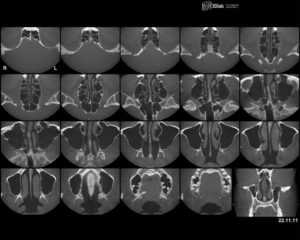

Компьютерная томография

Компьютерная томография (КТ) - это разновидность рентгеновского исследования, при котором результат предстает в виде послойного изображения тела человека. Для проведения КТ человек подвергается ионизирующему облучению. При том, что информативность компьютерной томографии на порядок превышает обычное рентген-исследование, доза излучения этих методов диагностики практически идентична и находится в пределах 10-15 мЗв.

Для компьютерной томографии используют специальный аппарат, в который и помещается пациент. Установка включает в себя источник рентгеновского излучения, а также многочисленные датчики. Датчики фиксируют изменения луча после прохождения тканей организма и передают все данные на компьютер. Результат исследования предстает в виде многочисленных послойных снимков-"срезов".

Для диагностики сосудистого строения опухоли может использоваться компьютерная томография с контрастированием. Для этого пациенту вводят специальное вещество - контраст, которое делает изображение сосудов более отчетливым.

Современные мультиспиральные аппараты для КТ отличаются высокой скоростью получения изображений - все исследование длится не более 20-30 секунд. Эта особенность наиболее значима для визуализации пульсирующих объектов (сосудов, сердца), а также при обследовании некоторых групп пациентов, например детей, для которых достижение неподвижности - крайне непростая задача.